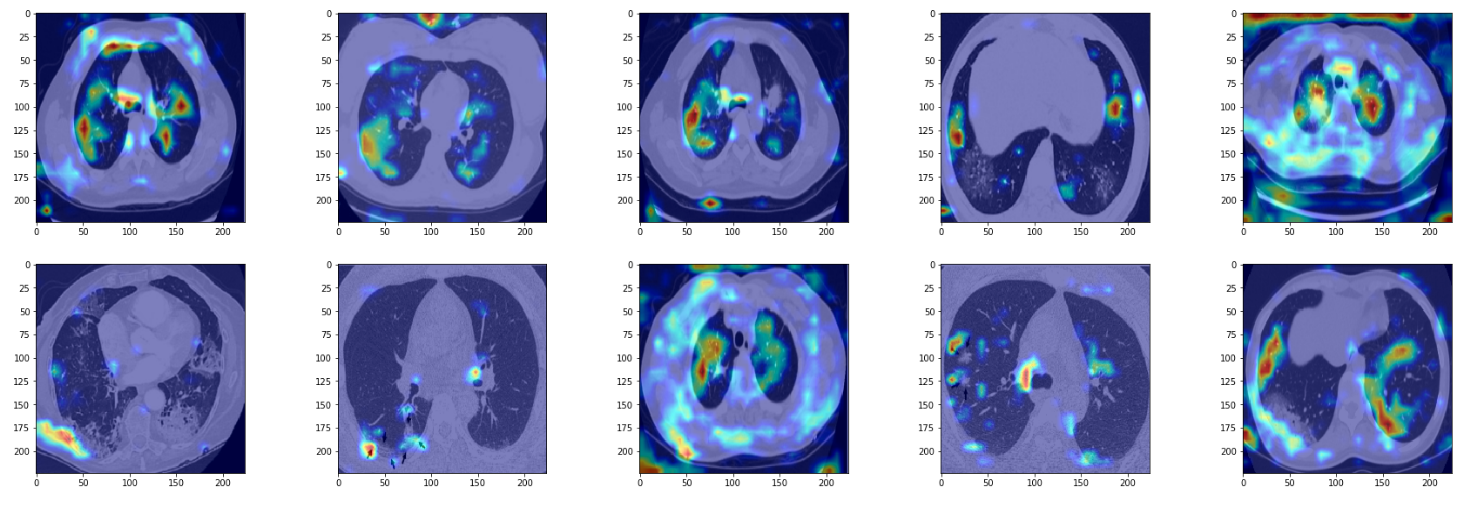

Let us now use the grad cam functionality to visualize a few examples from True positives, True negatives, False positives and False negatives.

True Positives

true_positives = np.logical_and(preds == 1, targets == 1)

true_positives = np.logical_and(true_positives, scores > 0.9)

true_positives_indices = np.nonzero(true_positives)

true_positives_paths = [metrics_dict['paths'][i] for i in true_positives_indices[0]]

true_positive_images = [do_grad_cam(x) for x in random.sample(true_positives_paths, 10)]

plt.figure(figsize=(30,15))

columns = 5

for i, image in enumerate(true_positive_images):

plt.subplot(len(true_positive_images) / columns + 1, columns, i + 1)

plt.imshow(image)

We see the model is able to focus on the ground-glass deformities that are characteristic of CT scans of COVID-infected patients. However, we also see that at times the network focuses on the boundary of the lung (in gray color) to make the decision. I am no radiologist to say whether we should be looking at the boundary to make the decision, but if not, then this is something that merits further inspection.